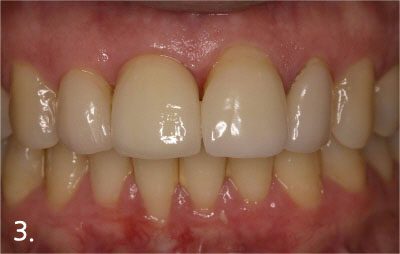

Implant crown was fabricated

All implant crowns were fabricated and delivered. All teeth functions were restored.

Implant placement and crown fabrication were completed without any complication